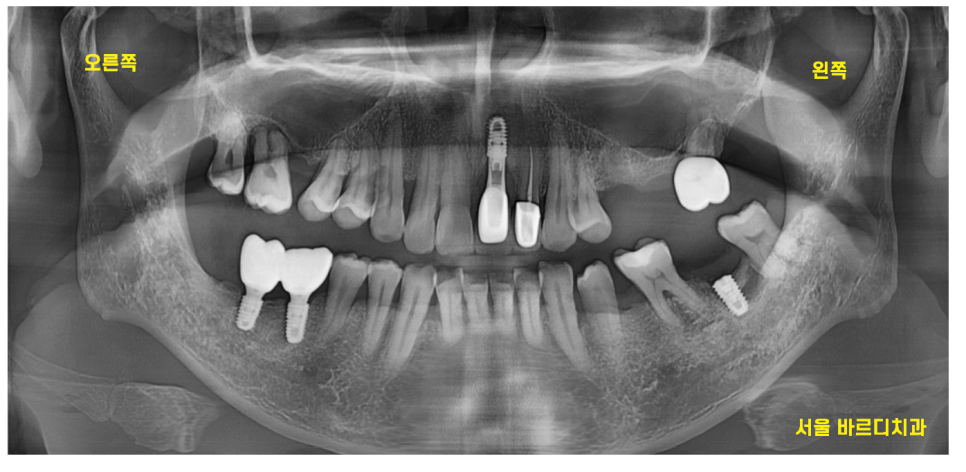

22.12.03

왼쪽 위 임플란트 심고 싶어서 왔어요.

상악동 거상술인가?

뼈를 만들어야 한다는데 다른 병원에서는 못한대요.

처음 저희 병원을 방문하셨을 때

말씀하셨던 내용입니다.

파노라마 사진상에서도 매우 얇아 보였습니다.